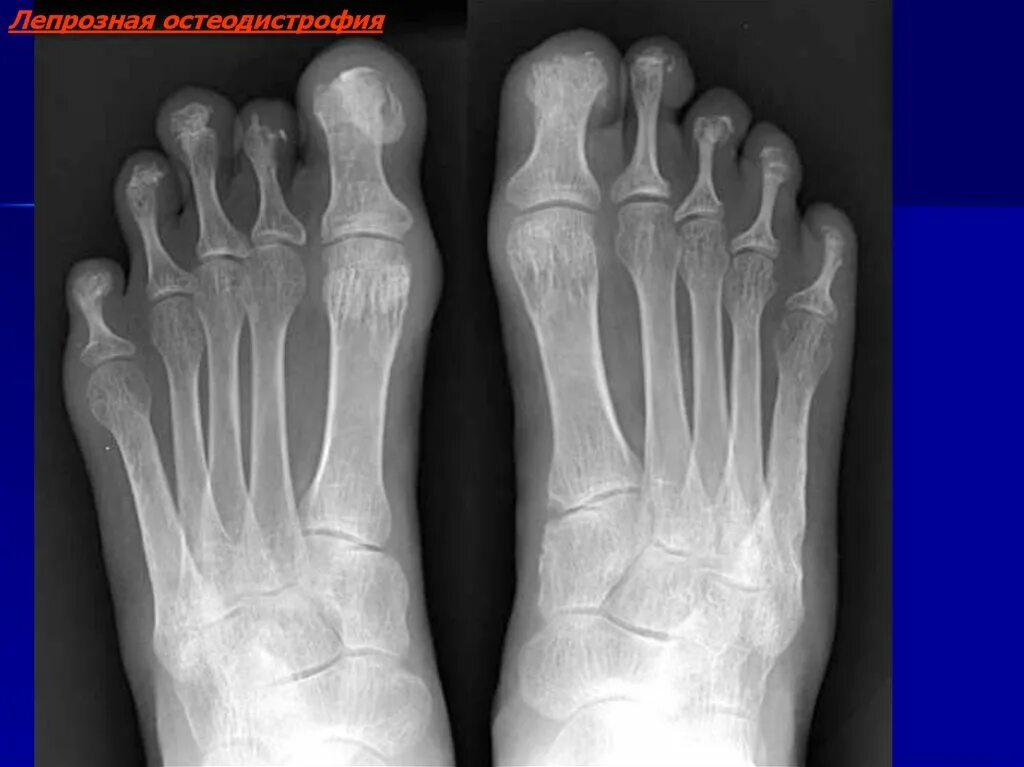

Изменение скелета